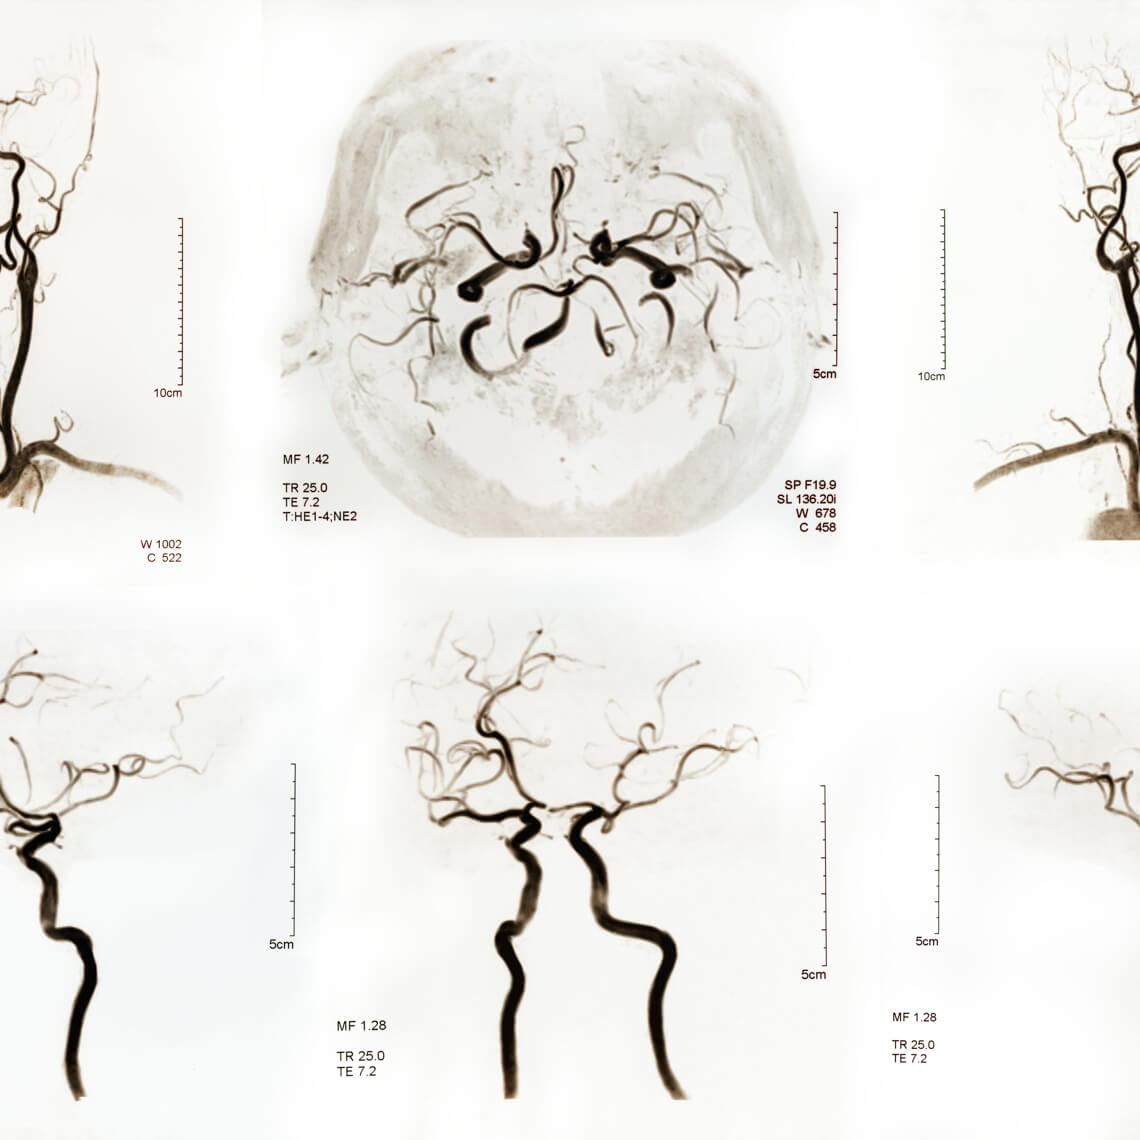

Assessing and treating patients presenting with symptoms related to ischemic stroke, and, in particular, vertebrobasilar stroke.

The AMC PSO has recently convened subject matter experts and ED clinical leaders to address challenges in assessing and treating patients presenting with symptoms related to ischemic stroke, and, in particular, vertebrobasilar stroke.